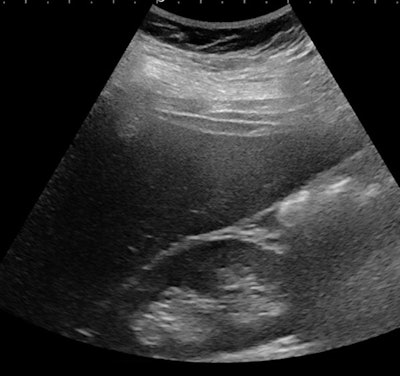

Échographie d'une jeune fille de 14 ans souffrant d'obésité sévère (indice de masse corporelle [IMC], 42 kg / m2). Il existe une hépatomégalie associée à une augmentation de l'échogénicité hépatique par rapport au rein droit et à une atténuation correspondant à une stéatose sévère. Ci-dessous, le même patient présente une augmentation du ratio foie / reins. Toutes les images avec l'aimable autorisation de Pr Stéphanie Franchi-Abella, PhD.La détection précoce est importante, car le régime alimentaire peut inverser le processus au début de la maladie. Cependant, la détection et la quantification de la teneur en graisse du foie et de la fibrose et de l'inflammation associées, indispensables au diagnostic de la NASH, restent difficiles chez les enfants; L'échographie en mode B reste relativement limitée pour le diagnostic de stéatose hépatique, la teneur en matières grasses devant être supérieure à 20%, mais la quantification n'est pas encore disponible comme outil clinique de routine sur les échographes, selon le Pr Franchi-Abella.